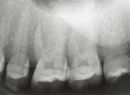

- Acquire basic X-Ray techniques such as film angle and projection angle for each area

- Free-moving finger arm allows you to hold the film at the position of your choice so you can practice 10 or 14 exposure techniques

10 Exposure Method